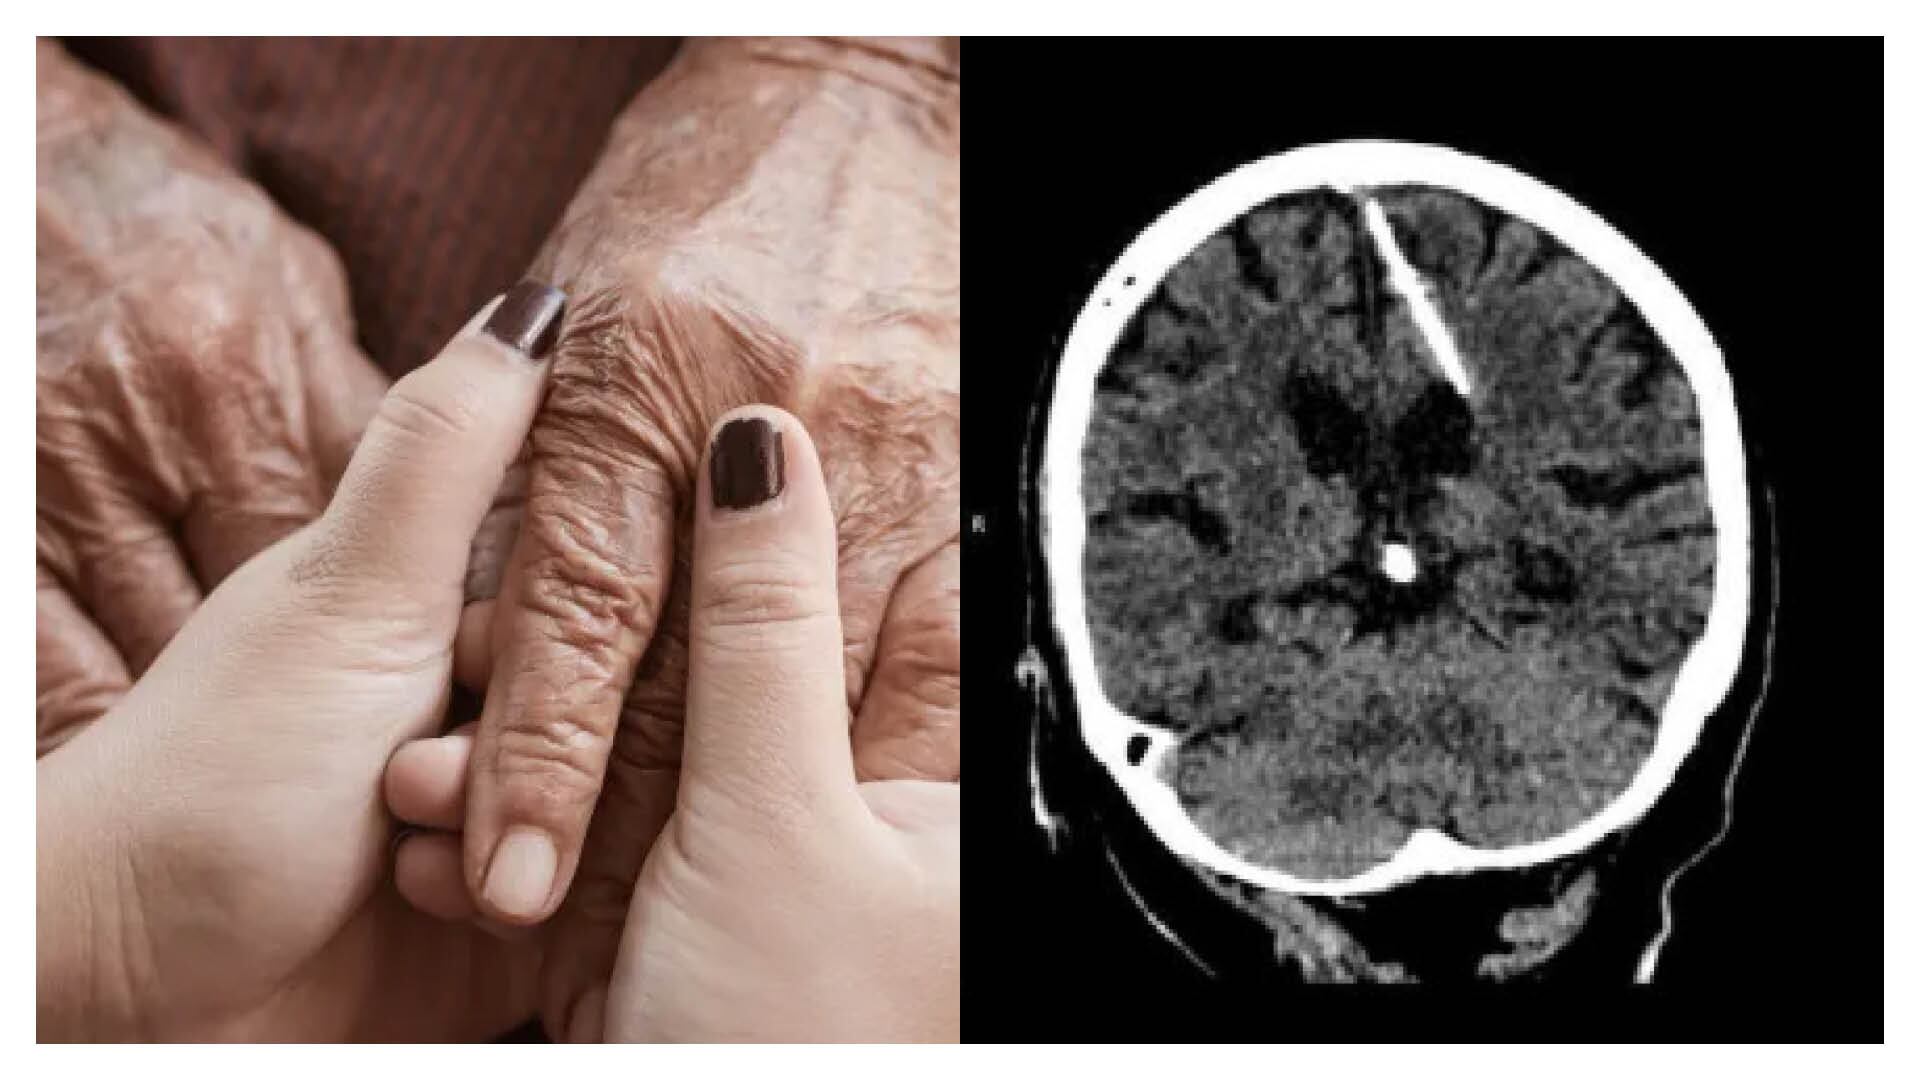

El Ministerio de Sanidad de la región de Sajalín, perteneciente a un isla rusa en el mar de Ojotsk, reportó recientemente un caso particular y para nada común en la región. Una anciana que fue a tratarse a un centro médico descubrió que llevaba incrustada una aguja en el cerebro gracias a una tomografía computarizada que le practicaron en la unidad.

Todavía no se conoce qué llevó a la mujer a acudir al hospital, pero sí se sabe que ella no tenía conocimiento de portar ese cuerpo extraño en su cabeza. La exploración por TAC reveló accidentalmente una aguja de tres centímetros clavada en el lóbulo parietal izquierdo de la paciente.

Contra todos los pronósticos, esto no tuvo consecuencias negativas en la salud de la mujer, pues nunca sufrió de dolores de cabeza. “La salud de la paciente no corre peligro, su estado está bajo control del médico tratante. Se decidió no someterse a una cirugía, ya que esto sólo podría empeorar su condición”, informó la entidad a través de su canal oficial de Telegram.

Así, cuando era bebé, la paciente fue sometida a un mortal proceso a manos de sus progenitores. El procedimiento era el siguiente: “se insertaba una fina aguja en la fontanela del bebé, lo que dañaba el cerebro. La fontanela se cerraba rápidamente, ocultando las huellas del crimen, y el bebé perdía la vida”, explica el ministerio.

Sin embargo, la pequeña sobrevivió solo para encontrar 80 años después aquel objeto en su cerebro.